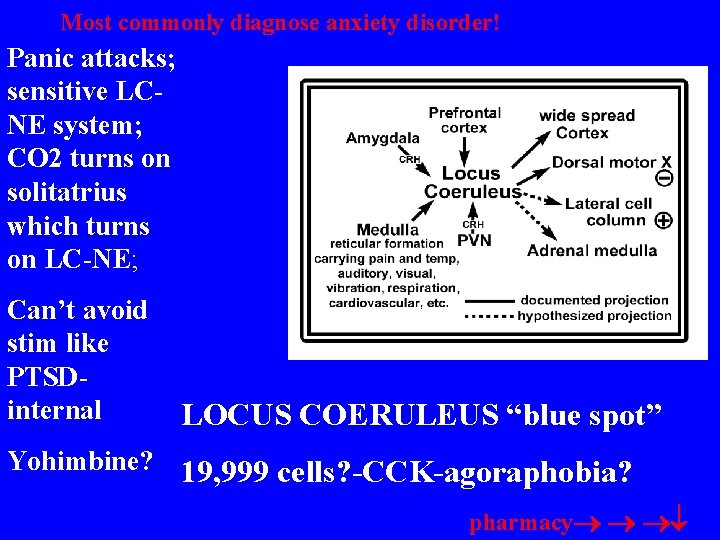

Most commonly diagnose anxiety disorder! Panic attacks; sensitive LCNE system; CO 2 turns on solitatrius which turns on LC-NE; Can’t avoid stim like PTSDinternal LOCUS COERULEUS “blue spot” Yohimbine? 19, 999 cells? -CCK-agoraphobia? pharmacy